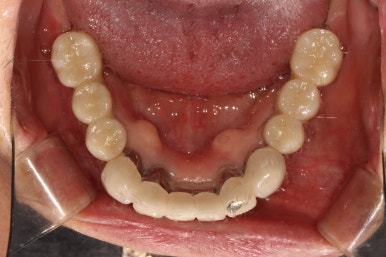

저희 치과와 협업하는 기공소에서 제작해온 임시치아를 장착한 상태입니다.

플라스틱 재질인 레진으로 제작되어 있어 색상은 그닥 수려하지 않으나, 연습용으로 써보기에는 아주 딱이죠?

생각보다 보기에 모양도 괜찮습니다. 요새 임플란트 보철물은 모두 CADCAM으로 지르코니아 블럭을 깎아서 제작하기 때문에, 만약 이 임시치아가 마음에 드셨다면 최종 지르코니아 크라운도 컴퓨터에 입력된 데이터를 이용하여 똑같이 깎아서 제작해드릴 수 있답니다. 이 모든게 치과에서 구강스캐너를 사용하기에 가능하죠..

어쨌든, 어금니 임플란트로 치아가 6개나 새로 제작되었기에 볼이나 혀가 씹히진 않는지 - 식사시에 아프거나 음식이 끼는 것은 없는지 등을 확인하기 위해 약 2-4주 정도 사용해보시게 됩니다.